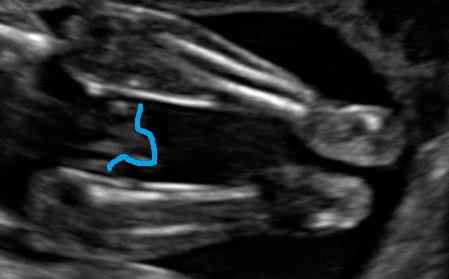

I'm going to guess boy from that last pic, can't tell from the other pics.

In last pic, you think it boy part or cord?

Thanks for answers. Just confusing -- from potty shot ,if its boy part, how come its so big/ long :) ...

Last one definitely looks like a normal baby boy to me.